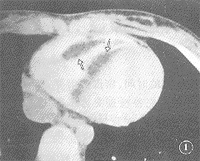

图1 病例1,室间隔右室侧与右室前壁间分叶状低密度占位(

),增强后CT值-34~-95 HU 图2 与图1同一病例,三维重建,显示肿瘤(

手术证实的7例非粘液性良性肿瘤,包括2例浸润性脂肪瘤,1例淋巴管瘤,2例纤维瘤,1例横纹肌瘤,1例二尖瓣前叶间皮瘤(见附表、附图1~8)。EBCT提示2例浸润性脂肪瘤为室壁或/和室间隔的壁在性占位,增强后CT值为-34~-101 HU;三维重建,可见瘤体起自心室壁推移冠脉或向心腔沿伸。2例纤维瘤起自左房后壁或室间隔,呈大分叶状或卵圆形,突向心腔,增强后CT值60~73 HU。横纹肌瘤1例,EBCT提示其起自于房、室间隔,呈多发结节状突向右心,强化后CT值约95 HU。淋巴管瘤1例亦为左室游离壁的壁在性肿瘤,增强后CT值为0~15.8 HU,该6例EBCT均提示较特征性的CT表现,结合临床均做出准确的组织病理学诊断,准确性为85.7%(6/7)。1例手术病理证实为二尖瓣前叶间皮瘤的病例,EBCT准确提示肿瘤位置、形状、大小与附着,因表现极似粘液瘤而定性为粘液瘤。2例术后复查同时提示胸腔积液与肺不张。

本组7例EBCT检查,在与超声心动图同样提示了心脏肿瘤位置、大小等方面征象的基础上,以不同的CT值提示了不同的病理学基础。如病例Ⅰ、Ⅱ瘤体增强后CT值仍为-34~-101 HU的脂肪密度而提示脂肪源性肿瘤,病例Ⅲ、Ⅳ瘤体CT值为60~73 HU,提示纤维实体肿瘤,病例Ⅴ、Ⅵ增强后CT值分别为平均95 HU的高密度及0~15.8 HU的水样密度,提示为血供丰富的横纹肌瘤与含水样物质的淋巴管瘤。病例Ⅰ、Ⅱ的EBCT三维重建,再现了肿瘤与心腔、心包或冠脉的空间关系。病例Ⅲ和病例Ⅴ的EBCT单层扫描同时显示了术后肺不张与胸腔积液。由于EBCT设备昂贵,国内外应用尚不普及,但其优越性将日益受到重视。

文献报道,在心脏非粘液瘤性良性肿瘤中,脂肪瘤最常见。本病在本组占2例(29.9%),亦属最多。肿瘤可发生于所有年龄,无性别差异。瘤体可完全位于心肌内,也可向心腔内外突出;可由成熟脂肪细胞和颗粒细胞组成,在房间隔形成脂肪样肥厚,亦可如病例Ⅰ、Ⅱ,心肌纤维为片索状脂肪组织分隔,形成浸润性脂肪瘤,乳头肌亦见受累[1,2]。我们认为,发生于房间隔或心肌壁的近脂肪密度肿物,向心腔突入或推压心包,为心脏脂肪瘤的重要EBCT征象。